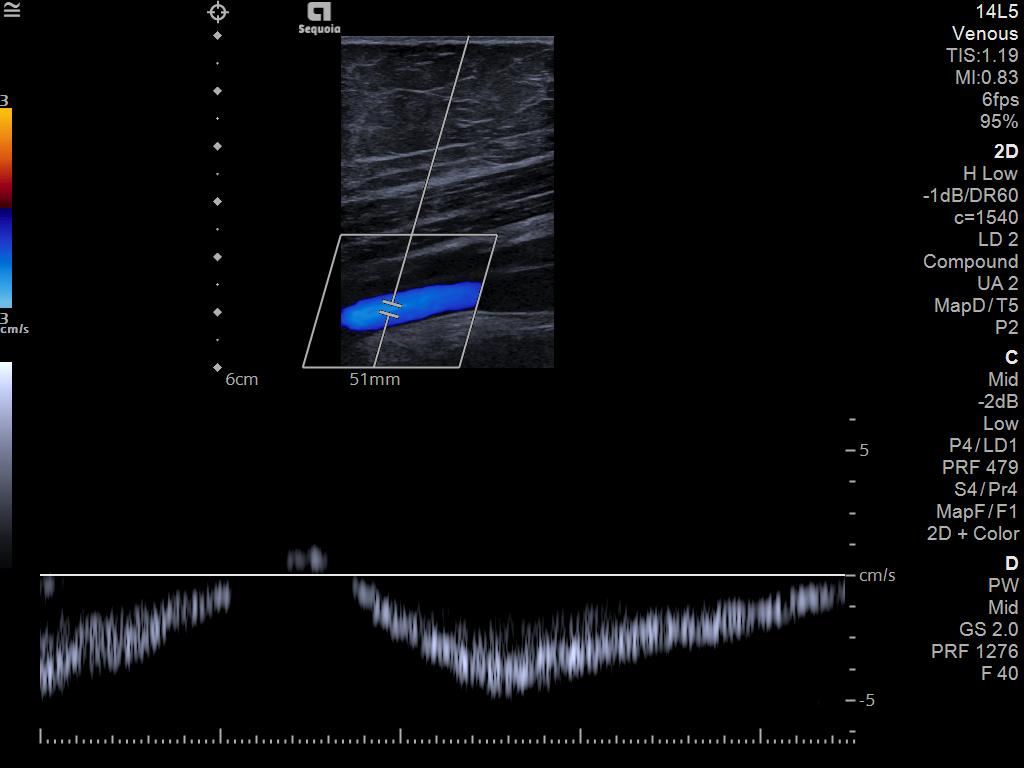

A clearer, deeper perspective with optimal acoustics for each clinical use case. Expand your assessment with advanced tools that take ultrasound beyond its traditional role.